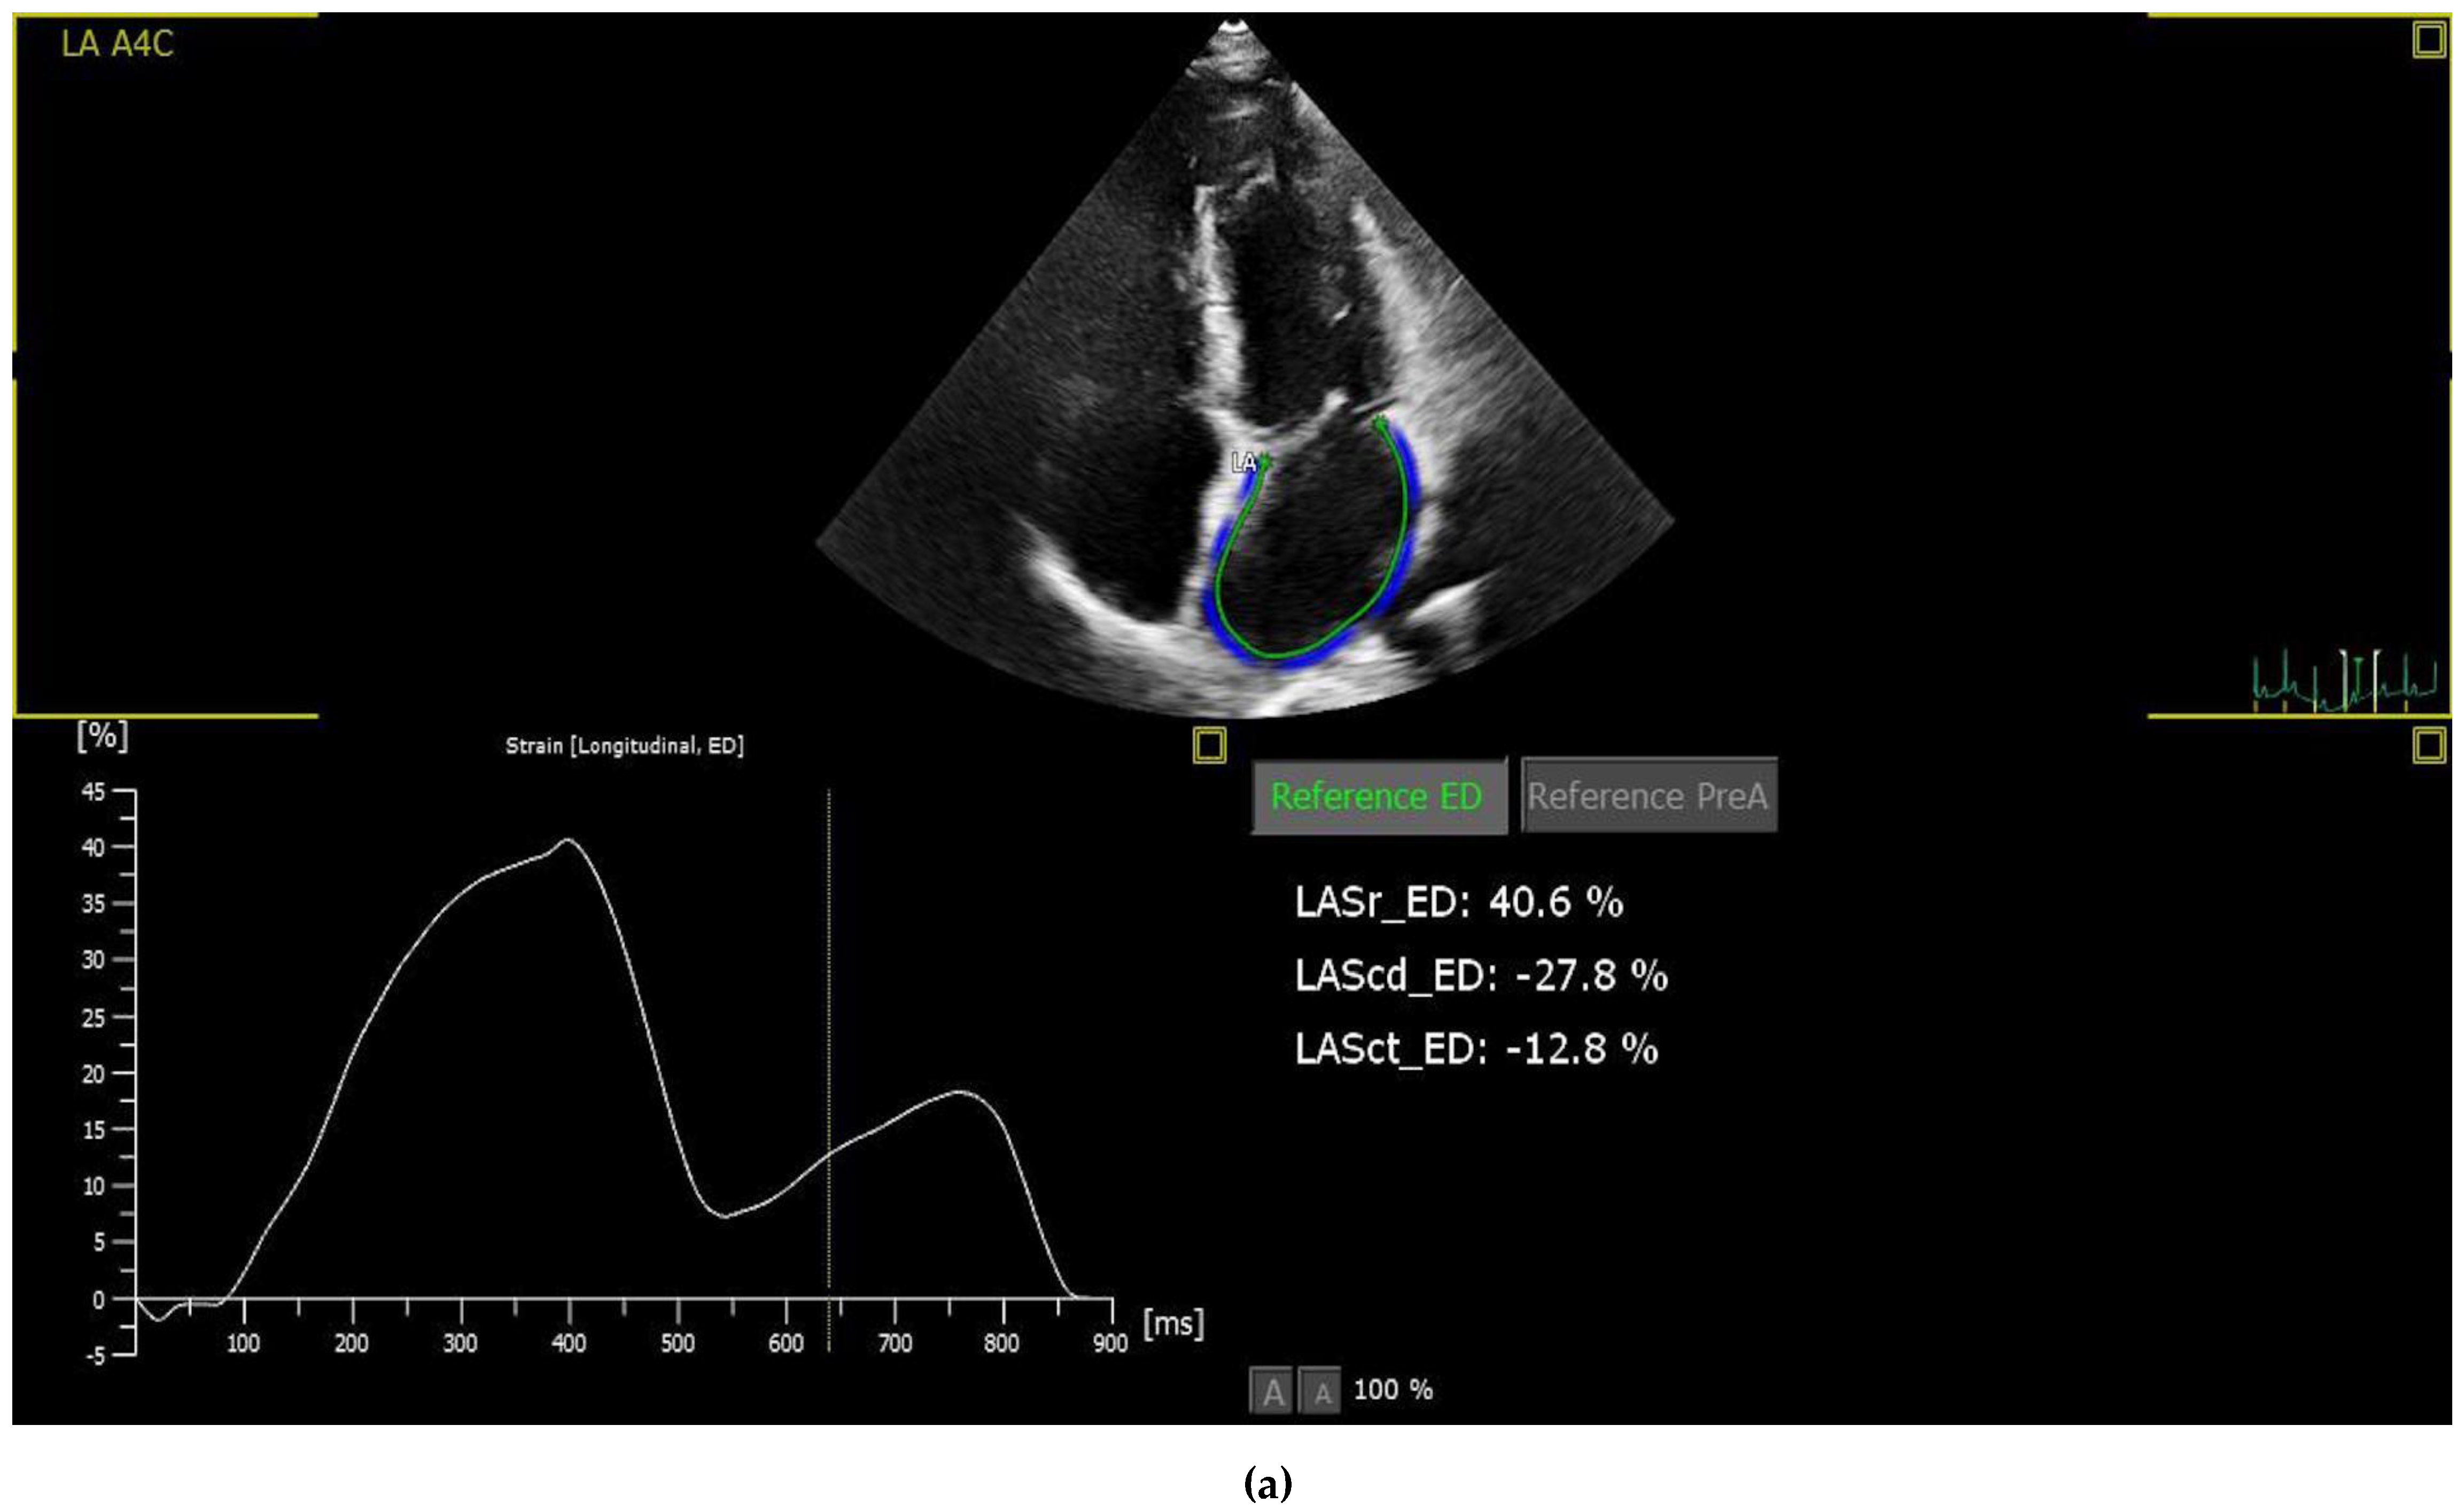

2.3. Strain Analysis

| LAS-r | 52.3 ± 15 | 44.5 ± 10.7 | 0.001 |

| LAS-cd | 36.9 ± 11.7 | 28.4 ± 9.7 | <0.001 |

| LAS-ct | 15.4 ± 9.4 | 16.1 ± 7.3 | 0.653 |